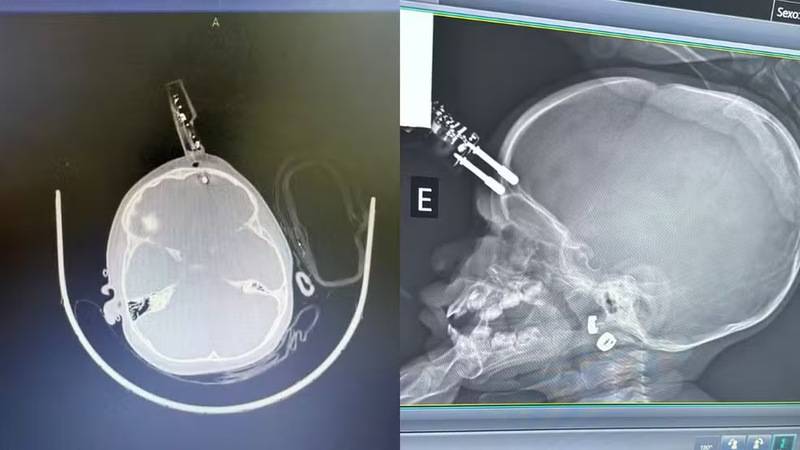

Uma menina de 1 ano e 4 meses ficou gravemente ferida após cair da cama e ter um pino de carregador de celular cravado na testa, em Divinópolis (MG). O objeto perfurou o crânio e atingiu o cérebro.

O acidente ocorreu na segunda-feira (12). A criança foi encontrada pela mãe com sangramento e precisou passar por cirurgia para retirada do pino, segundo o neurocirurgião que a atendeu.

O pino perfurou a região frontal da cabeça, perto do olho, e poderia ter causado perda da visão. Segundo o médico, o cérebro infantil tem grande capacidade de recuperação, reduzindo o risco de sequelas, mas lesões podem gerar cicatrizes e, no futuro, convulsões ou epilepsia. Apesar da boa evolução, a criança que já recebeu alta hospitalar, seguirá em acompanhamento neurológico.